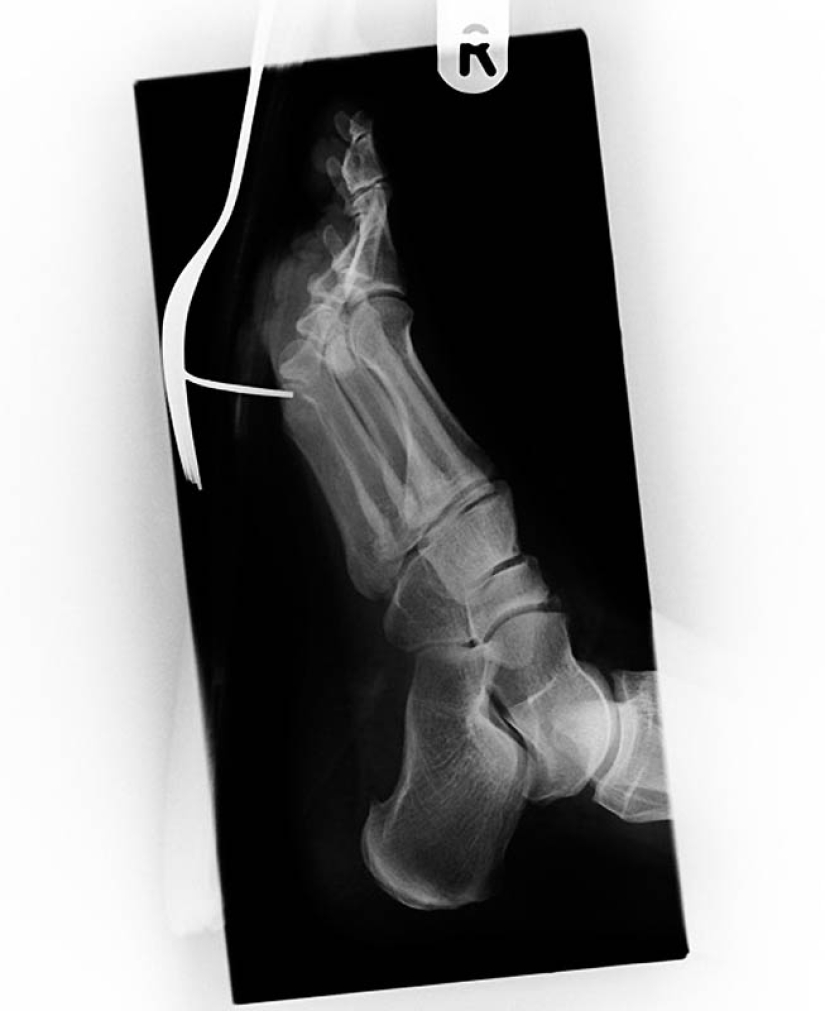

3. Antigua imagen de rayos X del pie de un soldado de la Guerra Anglo-Bóer (1899-1902) con una herida de bala. La bala se alojó en el hueso metatarsiano entre el pulgar y el segundo dedo.